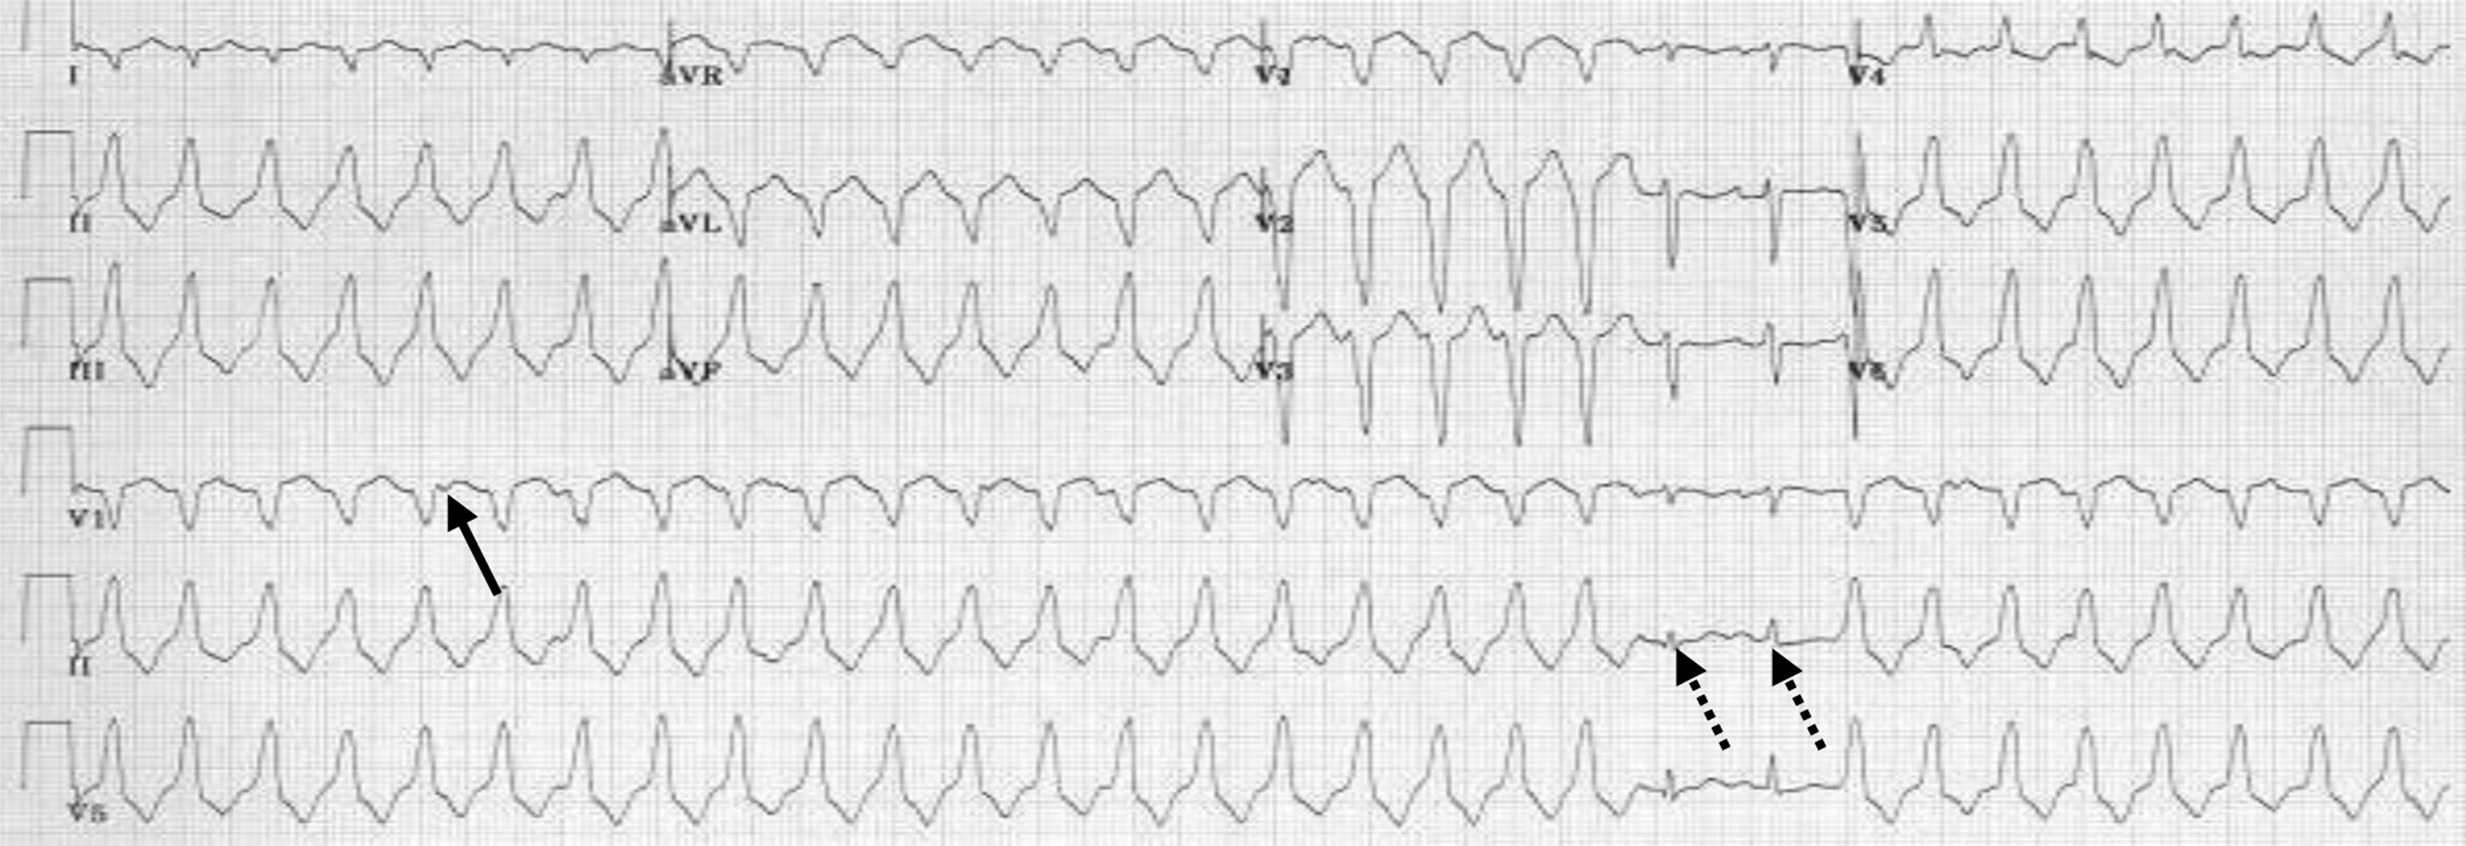

- les torsades de pointes sont une tachycardie irrégulière à QRS de largeur variable (polymorphe) et, surtout, ayant une polarité qui varie régulièrement en fonction du temps et qui tourne autour de la ligne isoélectrique. Cette dernière est observée en cas d’allongement de l’espace QT soit iatrogène soit congénital (fig. 6.24),

________________________________________________________________________________

Figure 6.24. Torsades de pointes.

Tachycardie irrégulière à QRS de largeur variable (polymorphe) et surtout ayant une polarité qui varie régulièrement en fonction du temps et qui tourne autour de la ligne isoélectrique.